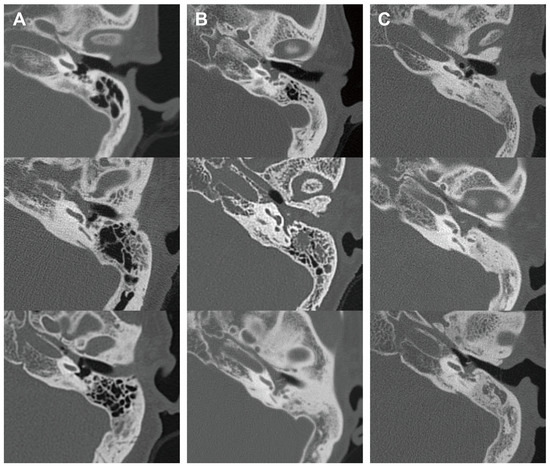

3.3. Diagnostic Performance of Blood Eosinophilia for EOM Compared to OME

In addition, we analyzed the radiological characteristics of EOM, GPA, and PCD patients for additional clinical clues. Two children in the PCD group and three patients in the GPA group did not undergo a temporal bone CT, and one patient in the EOM group had a post-mastoidectomy status decades ago. After excluding these patients, temporal bone CT images of 41 ears were subsequently analyzed. The CT images of the EOM group showed a distinctive feature of soft tissue density in the protympanum (near the Eustachian tube orifice and anterior to the promontory) (Figure 2 and Figure A1). The retrotympanum and mastoid cavity were less likely to be affected compared to the protympanum. Although there was no statistical significance (p = 0.096) in the proportion involving the protympanum between the groups, we found a significantly higher likelihood (p = 0.008) of having a soft tissue density exclusively in the protympanum of the EOM group (Table 3). The exclusive involvement of the protympanum was also significantly more frequent (p = 0.005) when compared to the OME group (Table A1). Interestingly, the PCD group showed significantly worse conditions in the mastoid cavity. All ears with PCD showed a soft tissue density in the mastoid (p = 0.009) with a severely sclerotic mastoid cavity (p < 0.001). In addition, the PCD group also had the highest chance of retrotympanum involvement (p = 0.029).

Figure 2.

Representative middle ear images in temporal bone computerized tomography of each disease group. Axial images at malleus umbo level are presented. Columns (A–C) indicate EOM, GPA, and PCD groups, respectively. EOM group showed soft tissue density in protympanic space and relatively clear retrotympanic space. (EOM: eosinophilic otitis media; GPA: granulomatosis with polyangiitis; PCD: primary ciliary dyskinesia.)

This study suggests that EOM can be preliminarily diagnosed based on blood eosinophilia before choosing to proceed with its pathological confirmation. A combined cut-off value of 6% in eosinophil concentration and a 450/μL eosinophil count showed a sensitivity of 100% and a specificity of 95.6% for diagnosing EOM among the control group consisting of OME patients who underwent ventilation tube insertion. In addition, the CT finding of soft tissue density exclusively in the protympanum was found in 41.2% of patients with EOM and was scarce in the patients with GPA (5.6%), PCD (0%), and OME (4.5%). Using these clinical cues, EOM can be distinguishable from the other diseases with refractory otitis media as well as OME, which is the most frequent.